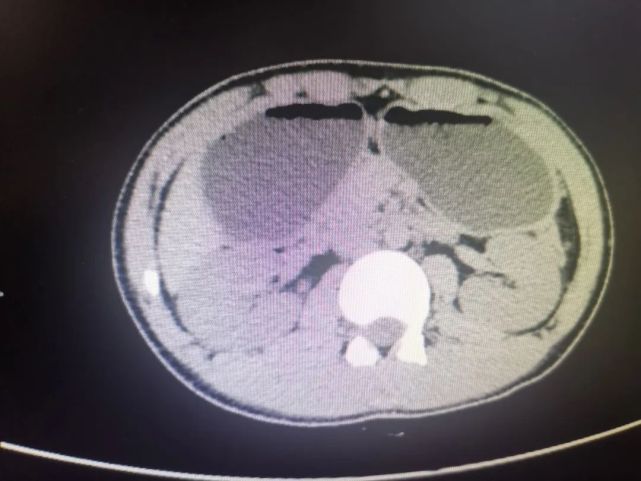

入院时,该患者神情疲乏,恶心呕吐不止,吃不好睡不好,形体消瘦,1米67左右的个子,体重只有50kg左右。”普内科主任陆为民介绍,全腹部CT显示,患者胃内有很多潴留液,一吃东西就吐,血液生化、动脉血气分析等检查结果显示,患者已经出现了急性肾功能损伤、代谢性碱中毒、低钾、低钠、高尿酸血症等症状。

▲全腹部CT显示,患者胃内有很多潴留液